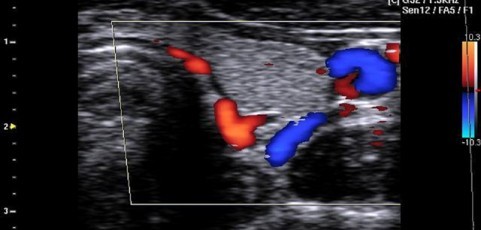

Рис. 26. Схема и ЦДК-изображение щитовидной железы при поперечном сканировании.

а -- правая доля; б -- левая доля;  1- правая доля ЩЖ, 2- левая доля ЩЖ

Рис. 27. Дуплексное изображение щитовидной железы. На фоне сонограммы ее левой доли  определяется цветное картирование  артерий и вен.